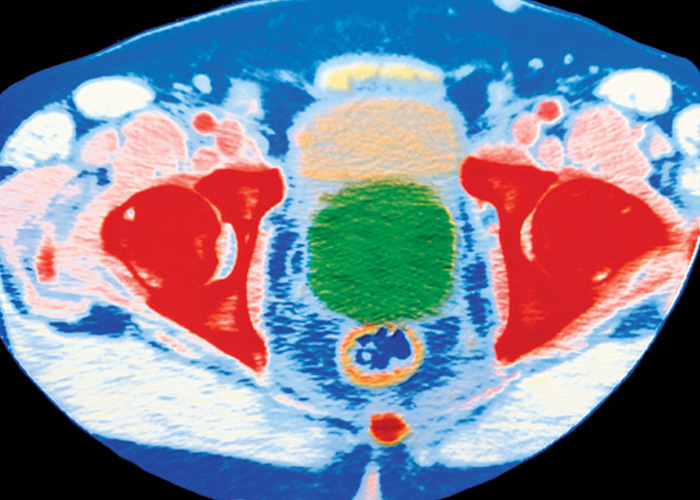

Once a cancer has been diagnosed, whether through a transrectal ultrasound, an MRI scan or a biopsy, other tests are then conducted to see if the cancer has spread within the prostate or to other parts of the body. Survival rates tend to be much higher if the disease is caught earlier and hasn’t spread further than the prostate.